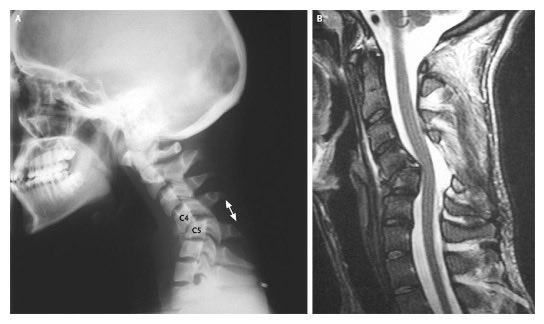

Шея с5 с6

Шея с5 с6 110 фотографий